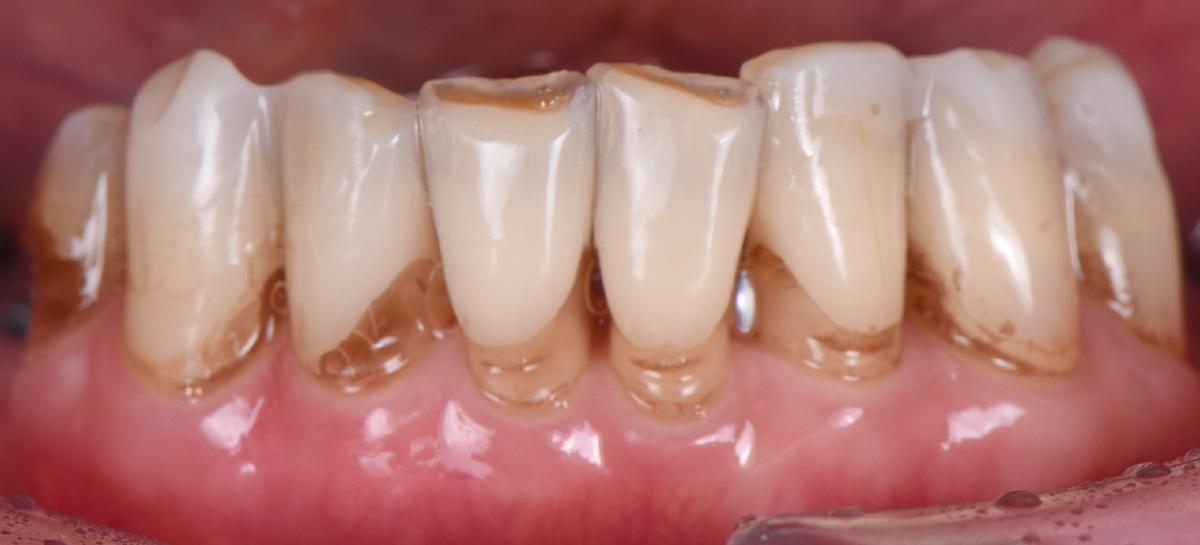

Как выглядит результат спустя несколько лет — на пяти фотографиях ниже

Верхний зубной ряд:

-

Справа. Протяженный мост на 5 единиц с опорой на 3 свои зуба

Передние зубы. Две одиночные коронки + мост на 3 единицы

Слева. 4 коронки с опорой на 4 импланта + зуб мудрости

Нижний зубной ряд:

Справа. Мост на 3 единицы с опорой на 2 импланта + дистопированный зуб мудрости

Передние зубы. 8 собственных +/- живых зубов

Слева. 1 свой зуб под коронкой, 2 коронки с опорой на 2 импланта + дистопированный зуб мудрости